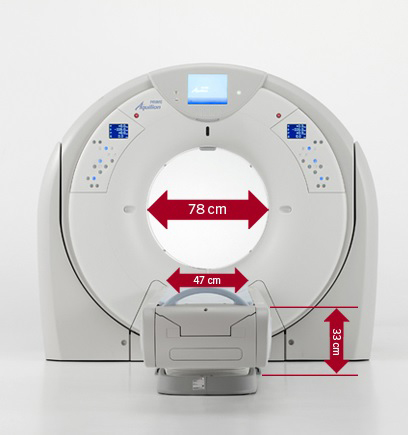

Характеристики аппарата:

- Гентри 78 см; 47 см ширина стола;

- Минимальная высота верхней части стола - 33 см;